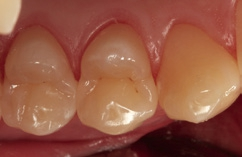

Fall 5 Minimalinvasive Slot-Versorgung an Zähnen 13 und 14

Die Zähne 13 und 14 des 19-jährigen Patienten zeigten aktive Primärläsionen, die Anzeichen der hohen Kariesaktivität des jungen Patienten waren (Abb. 20). Beide Kavitäten wurden mit dem Komet Mikropräparationsinstrument 8830M.314012 präpariert und die approximalen Flanken mithilfe eines diamantierten, wabenförmigen Feinkornfinierstreifens WS 25F (Komet Dental) geglättet. Die Abbildung 21 zeigt die beiden präparierten Kavitäten mit bereits angelegten Palodent V3-Spannringen und Teilmatrizenfolien. Der distal gelegene Spannring wurde von seinem Ringdurchmesser nach distal orientiert, um eine bessere Zugänglichkeit zu den beiden Kavitäten zu gewährleisten. Gerade im Prämolarenbereich ist dieses Vorgehen oftmals sehr hilfreich. Die Abbildung 22 zeigt die fertige Versorgung mit SDR flow+ in der Farbe A2 nach adhäsiver Vorbehandlung mit Prime&Bond active nach Schmelzkonditionierung mit Phosphorsäuregel. Generell ist bei den Universaladhäsiven der selbstkonditionierenden Vorbehandlung des Dentins der Vorzug zu geben. Eine selektive Schmelzätzung bei so schmalen und kleinen Kavitäten ist aber nicht so einfach umzusetzen. Ein Pluspunkt bei allen Universaladhäsiven ist deren Toleranz auf eine vorangegangene Ätzung des Dentins mit Phosphorsäuregel: Diese „Etch&Rinse“-Anwendung hat keinen negativen Einfluss auf die Randintegration und die Haftung. Eine Metaanalyse zu Universaladhäsiven attestiert den milden Universaladhäsiven sehr gute Haftwerte auf Dentin im selbstkonditionierenden Modus [48]. Eine zusätzliche Phosphorsäurekonditionierung ergibt hier keine Vorteile, da die Dentin-Haftwerte sich im selbstkonditionierenden und „Etch&Rinse“- Modus nicht unterscheiden [10,56], aber auch keine Nachteile. Auch dieses Beispiel zeigt die gute Farbadaptation und Randintegration des Bulk-Flow-Komposits.